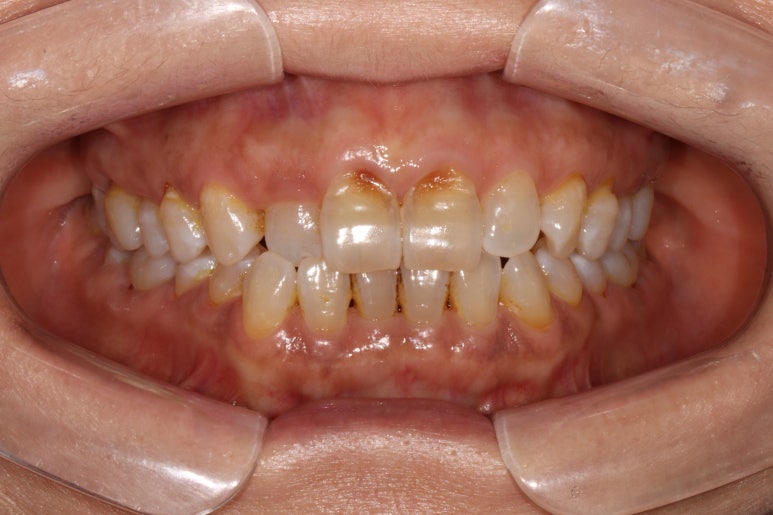

앞니의 치경부 마모가 눈에 띄긴 하지만, 전체적으로 쌓여있는 치석말고는 별 문제가 없었습니다.

화살표로 가리치고 있는 치아의 불편감을 호소하고 계셨습니다.

보시다시피, 아래턱 큰어금니의 씹는면에 약간의 충치가 있는바.. 일단 레진으로 떼우기로 치료계획을 세웠었죠.